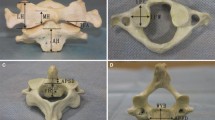

The cylinder was gradually thickened in the 3D reconstruction until it broke through the outer or inner wall of the superior articular process of the atlas (a, b), and this diameter of the cylinder was recorded. The implantation of the cylinder was simulated during the 3D reconstruction. The red portion is the length of the cylinder in the lateral mass of the axis, the yellow portion is the length of the cylinder in the atlantoaxial joint space, and the green portion is the length of the cylinder in the lateral mass of the atlas (c, d)

The axis length of new AATS (length A) was 8.5 ± 0.7 mm on the left side and 8.6 ± 0.6 mm on the right side; the length in the atlantoaxial articular process space (length B) was 6.6 ± 0.3 mm on the left side and 6.7 ± 0.4 mm on the right side; the length in the lateral mass of the atlas (length C) was 10.5 ± 0.6 mm on the left side and 10.6 ± 0.5 mm on the right side. According to the result of the measurement, the atlantoaxial CT data of a 30-year-old normal adult male were finally selected for the establishment of a finite element model (Table 2). To allow the cancellous bone to grow along the porous metal, the porous metal part needs to run through the atlantoaxial articular space and penetrates the cortical part of the inferior articular process of the atlas and the superior articular process of the axis. Therefore, when designing the screw, the lengths of the head and tail near the end of the porous structure needed to be reduced by 2 mm, which is the cortical thickness, while the length of the middle porous metal needed to be increased at both ends by 2 mm. To ensure the strength of the screw, the middle porous metal consisted of a solid cylinder structure. By measuring relevant atlantoaxial parameters and the individual differences of patients, the 3D printing technology is used to make new AATS suitable for patients. According to the design parameters, the new AATS which is suitable for this case was set as follows: diameter, 6 mm; length of the thread structure of the head, 10 mm; length of the middle porous metal, 8 mm (the middle porous structure contains a solid cylinder with an outer diameter of 3 mm and an inner diameter of 3 mm); length of the thread structure of the tail, 8 mm; and total length, 26 mm. A relevant finite element model was established for analysis (Fig. 5).